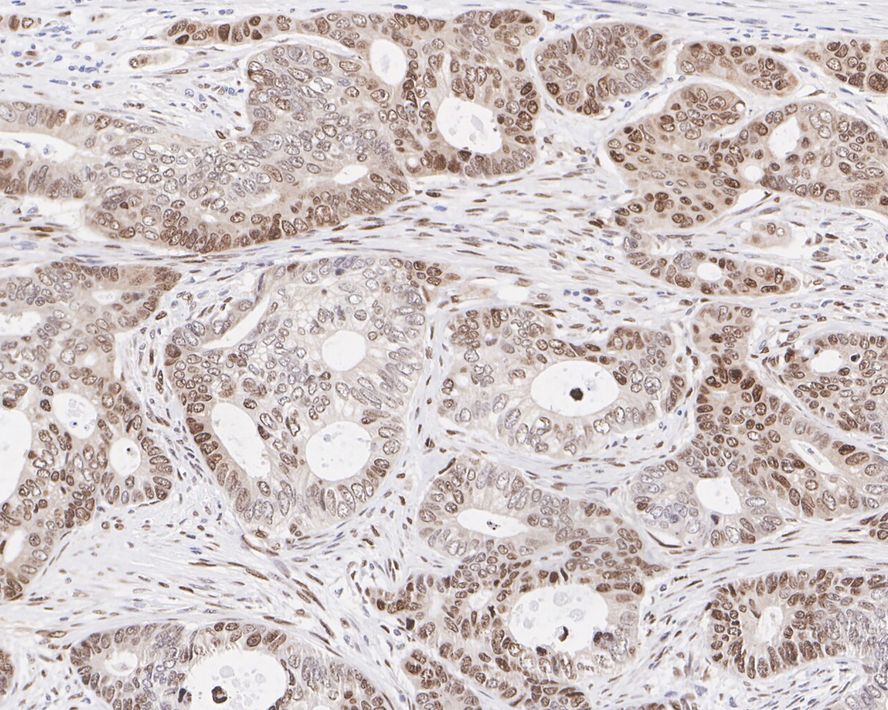

Catalog# HA722295

HMGA2 Recombinant Rabbit Monoclonal Antibody [PSH05-53]

IHC-P